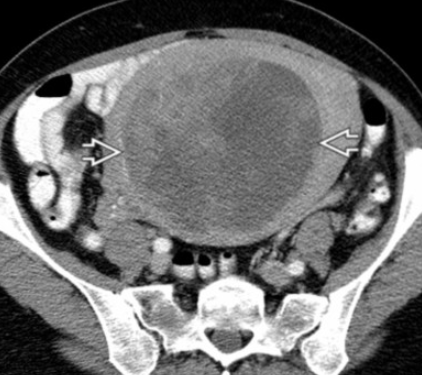

• CT A&P is preferred first test for staging

• MRI is degraded by bowel peristalsis motion and therefore is not preferred